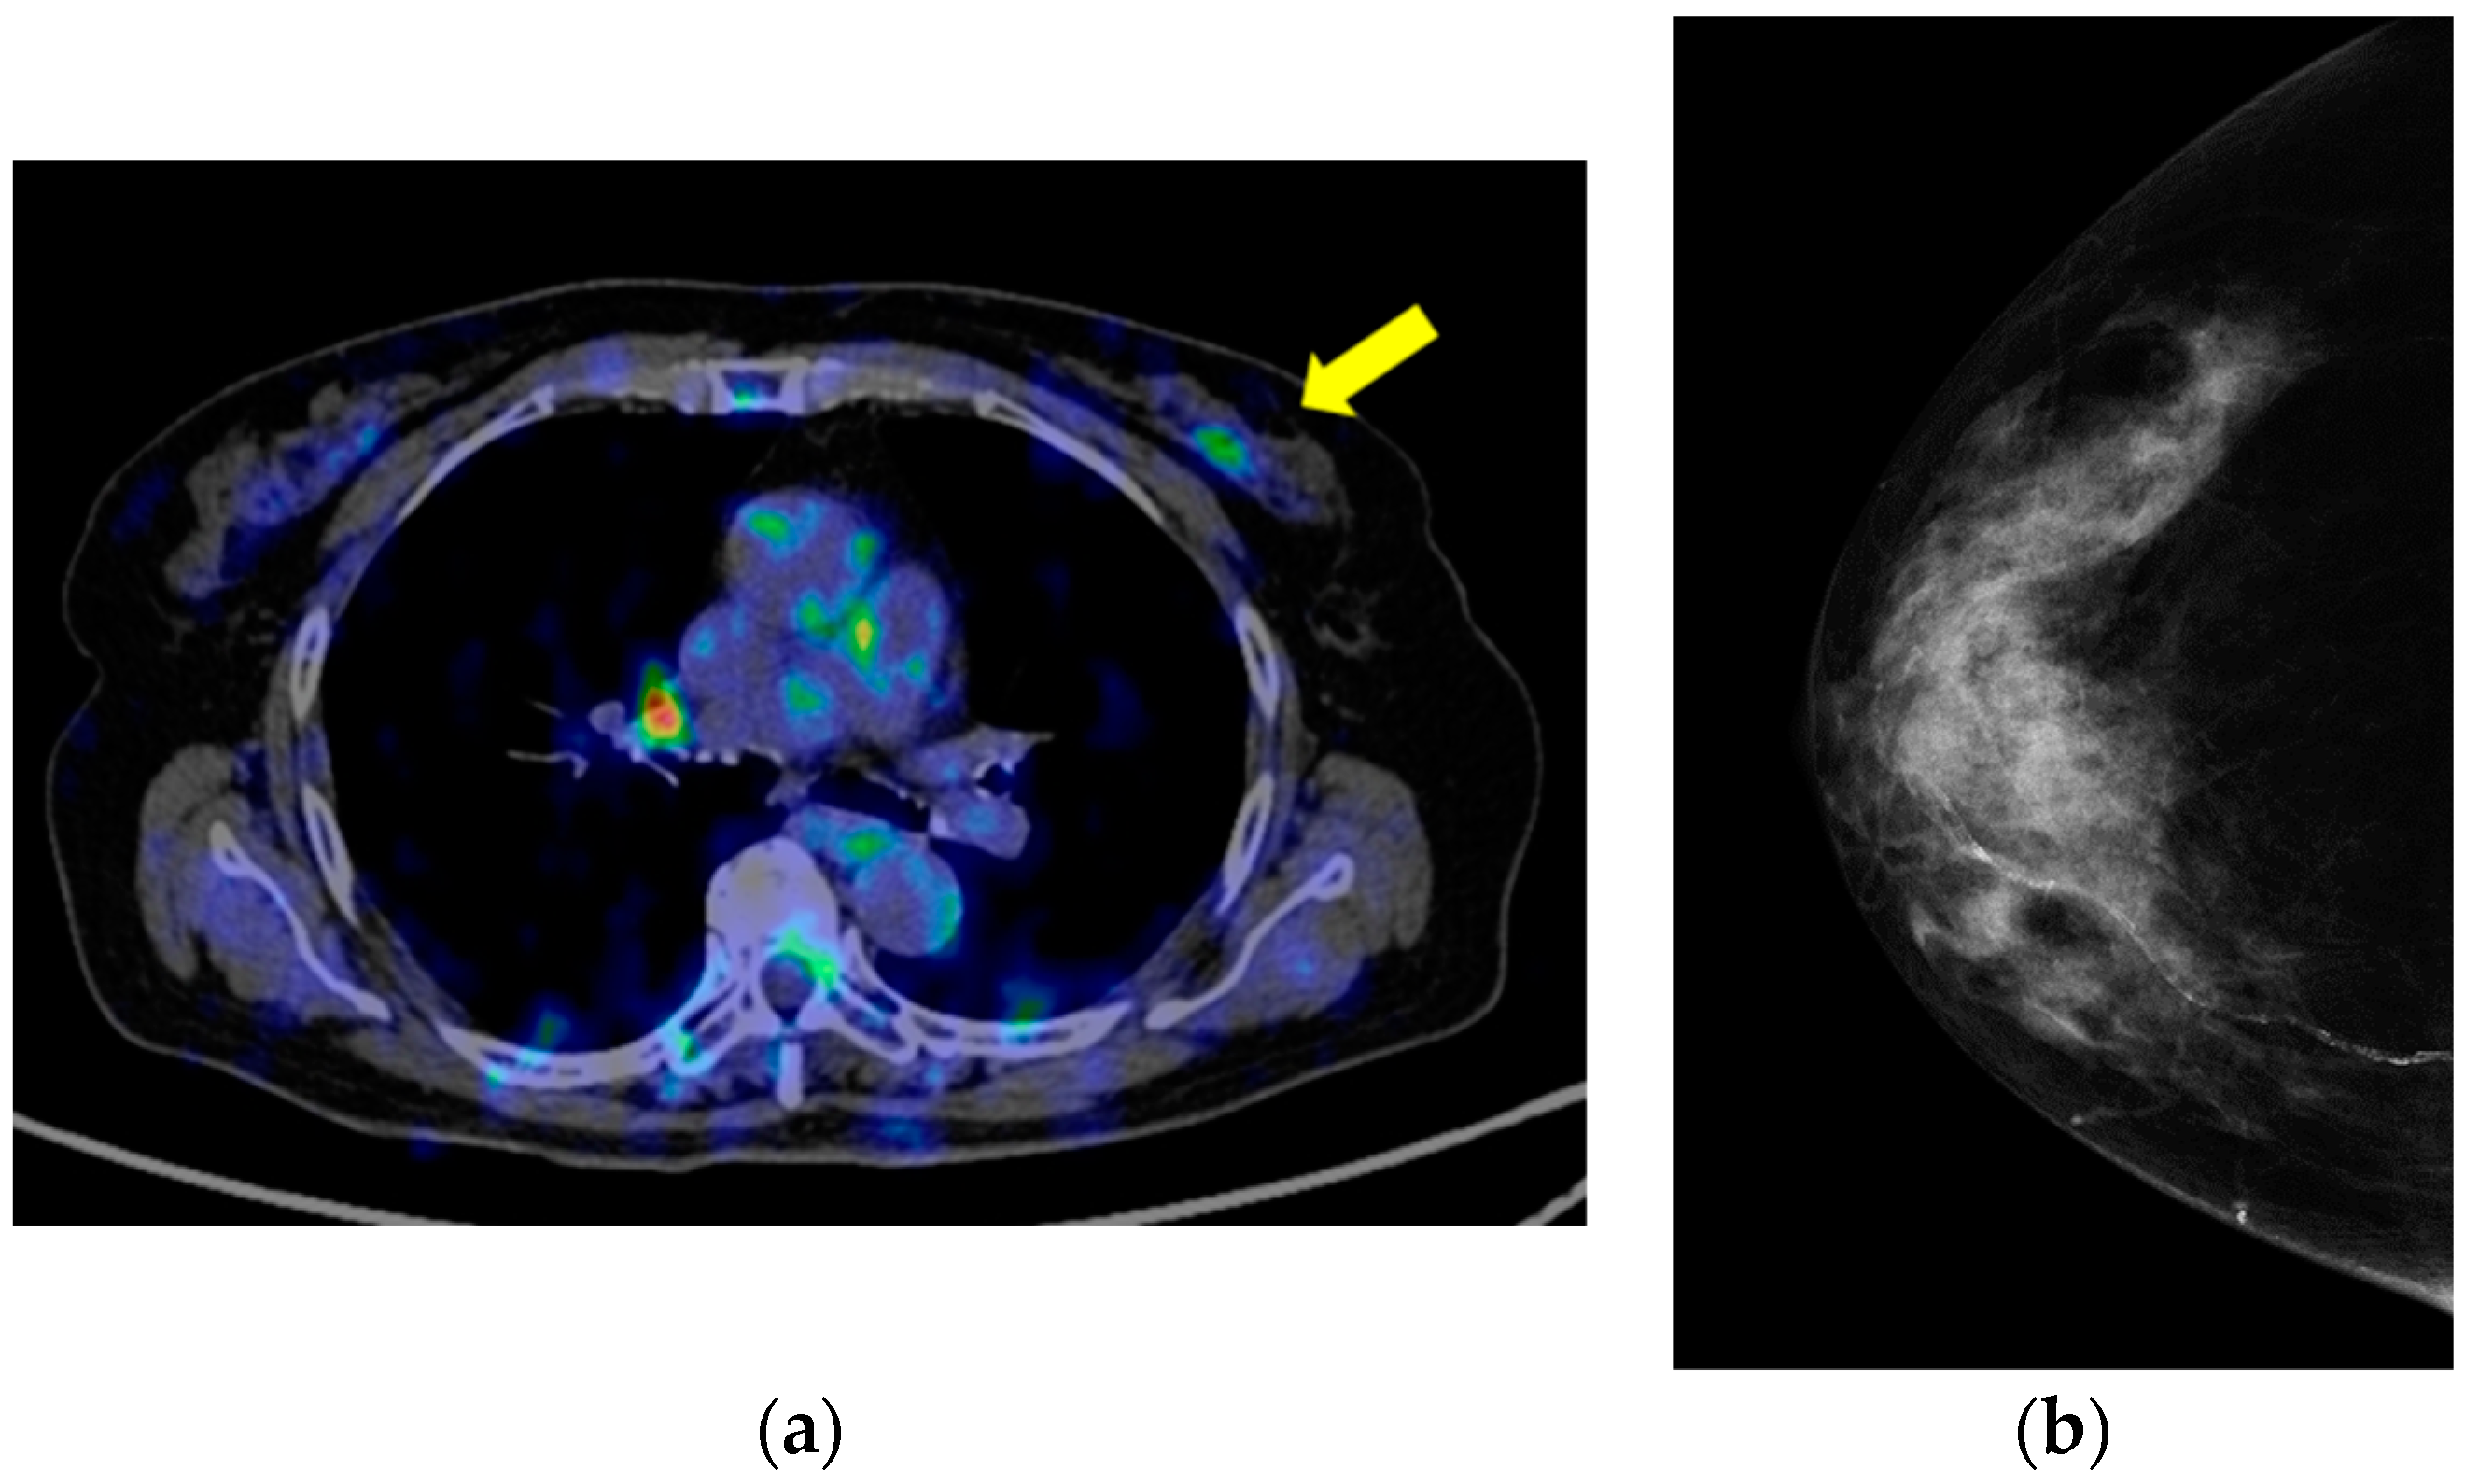

2. Case Presentation